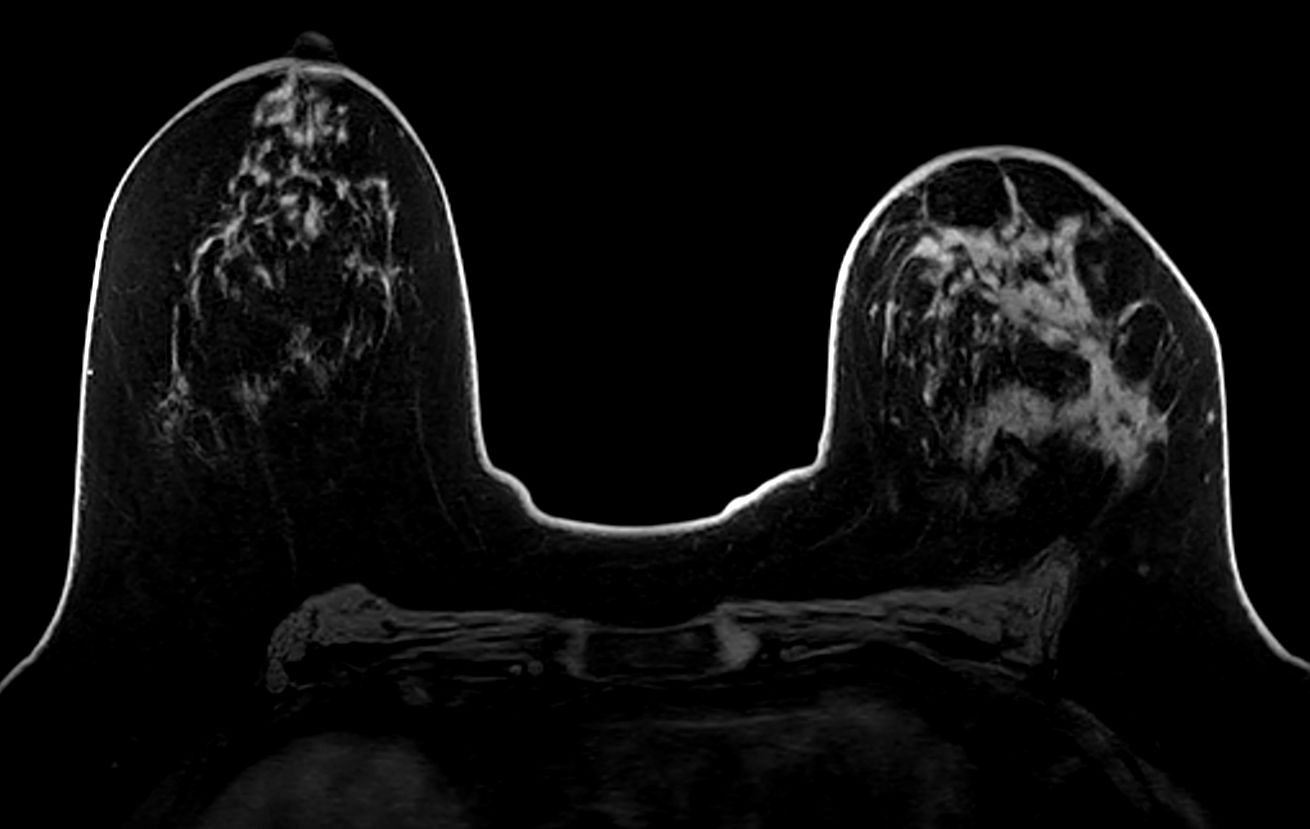

Axial T1w FFE

Axial T2w TSE

Axial T1w FFE mDIXON

Axial dynamic T1w FFE

Axial dynamic T1w FFE (subtraction)

Axial T1w FFE mDIXON (post-gado)

Axial T1w FFE mDIXON (post-gado) (MIP)